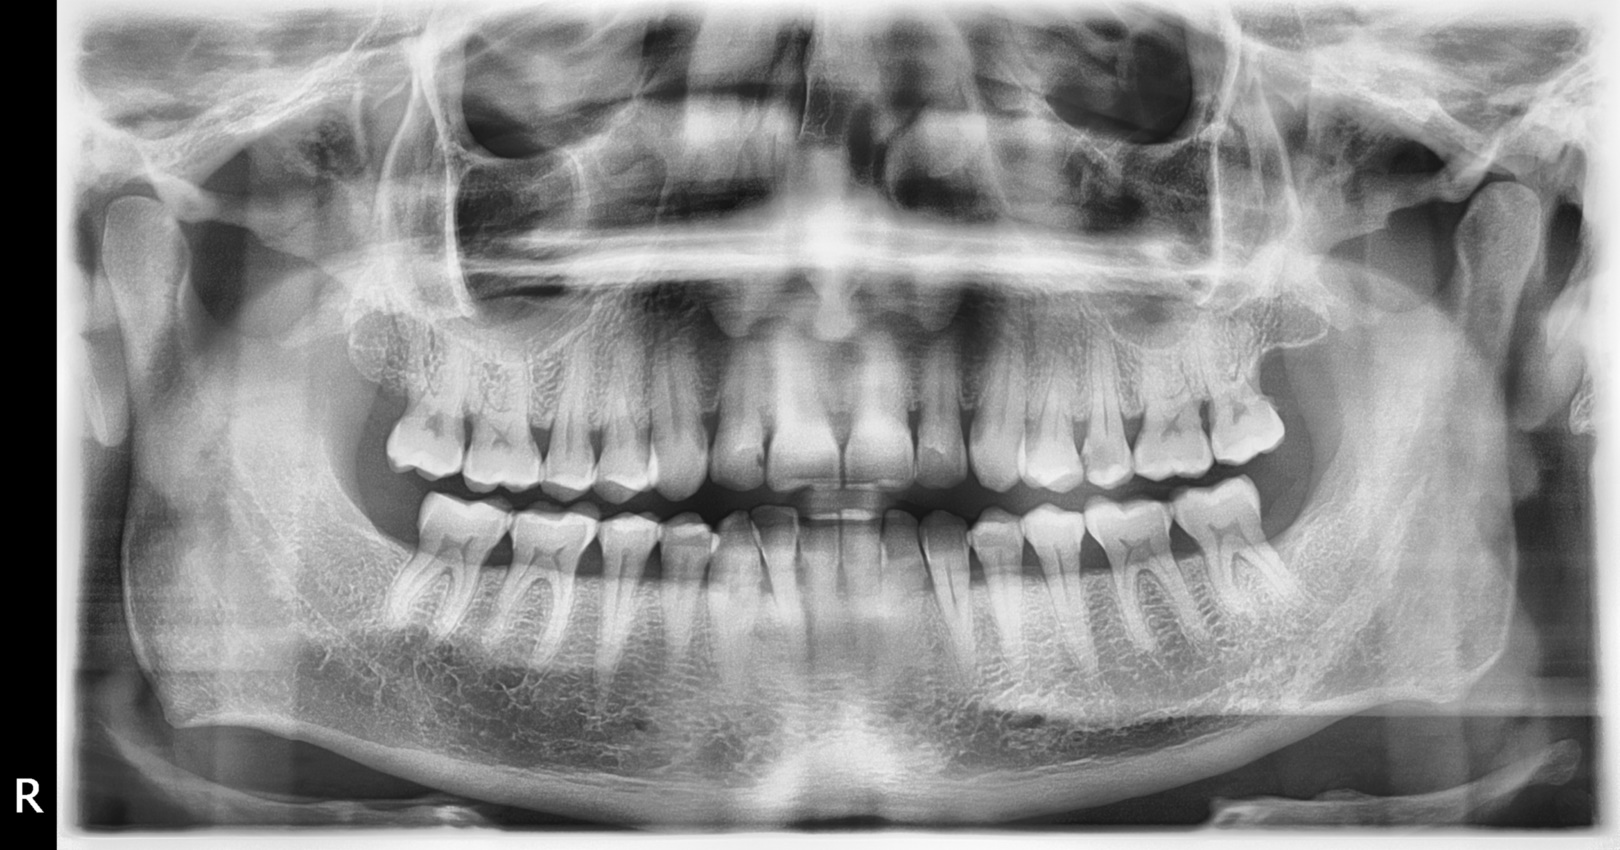

A DVT or CT scan is mostly used in maxillofacial surgery. In some cases, a 3D diagnosis is also required for orthodontic treatments. Prior to orthodontic surgery, an advance 3D diagnosis is mandatory. In any case, prior to an implant surgery, preliminary examinations must take place. First, a panoramic x-ray is taken. When evaluating the X-ray, it is decided which teeth must be replaced. Then it has to be judged whether there is enough bone mass to even place implants. Since the panoramic radiograph is a two-dimensional image showing only height and width, a 3D scan with CT or a volumetric tomograph must be performed to check the bone depth as well. Furthermore, only a CT scan allows an accurate measurement of the bone supply, on which the size of the implants to be used depends. In addition to the bone mass, the general state of health of the patient also plays a decisive role in determining whether appropriate treatment is possible. Circumstances that greatly affect the success of implant placement are e.g. Diabetes or heavy smoking.

The implants are planned after bone measurement or after a successful bone graft on the 3D image. The oral surgeon defines the positions of the implants and consequently the size of the implants to be used.

Even with complicated tooth removal, especially when removing wisdom teeth, a tooth CT scan may be necessary, because not infrequently these teeth have 4 or 5 roots whose position and shape cannot always be determined clearly based on the 2D image.